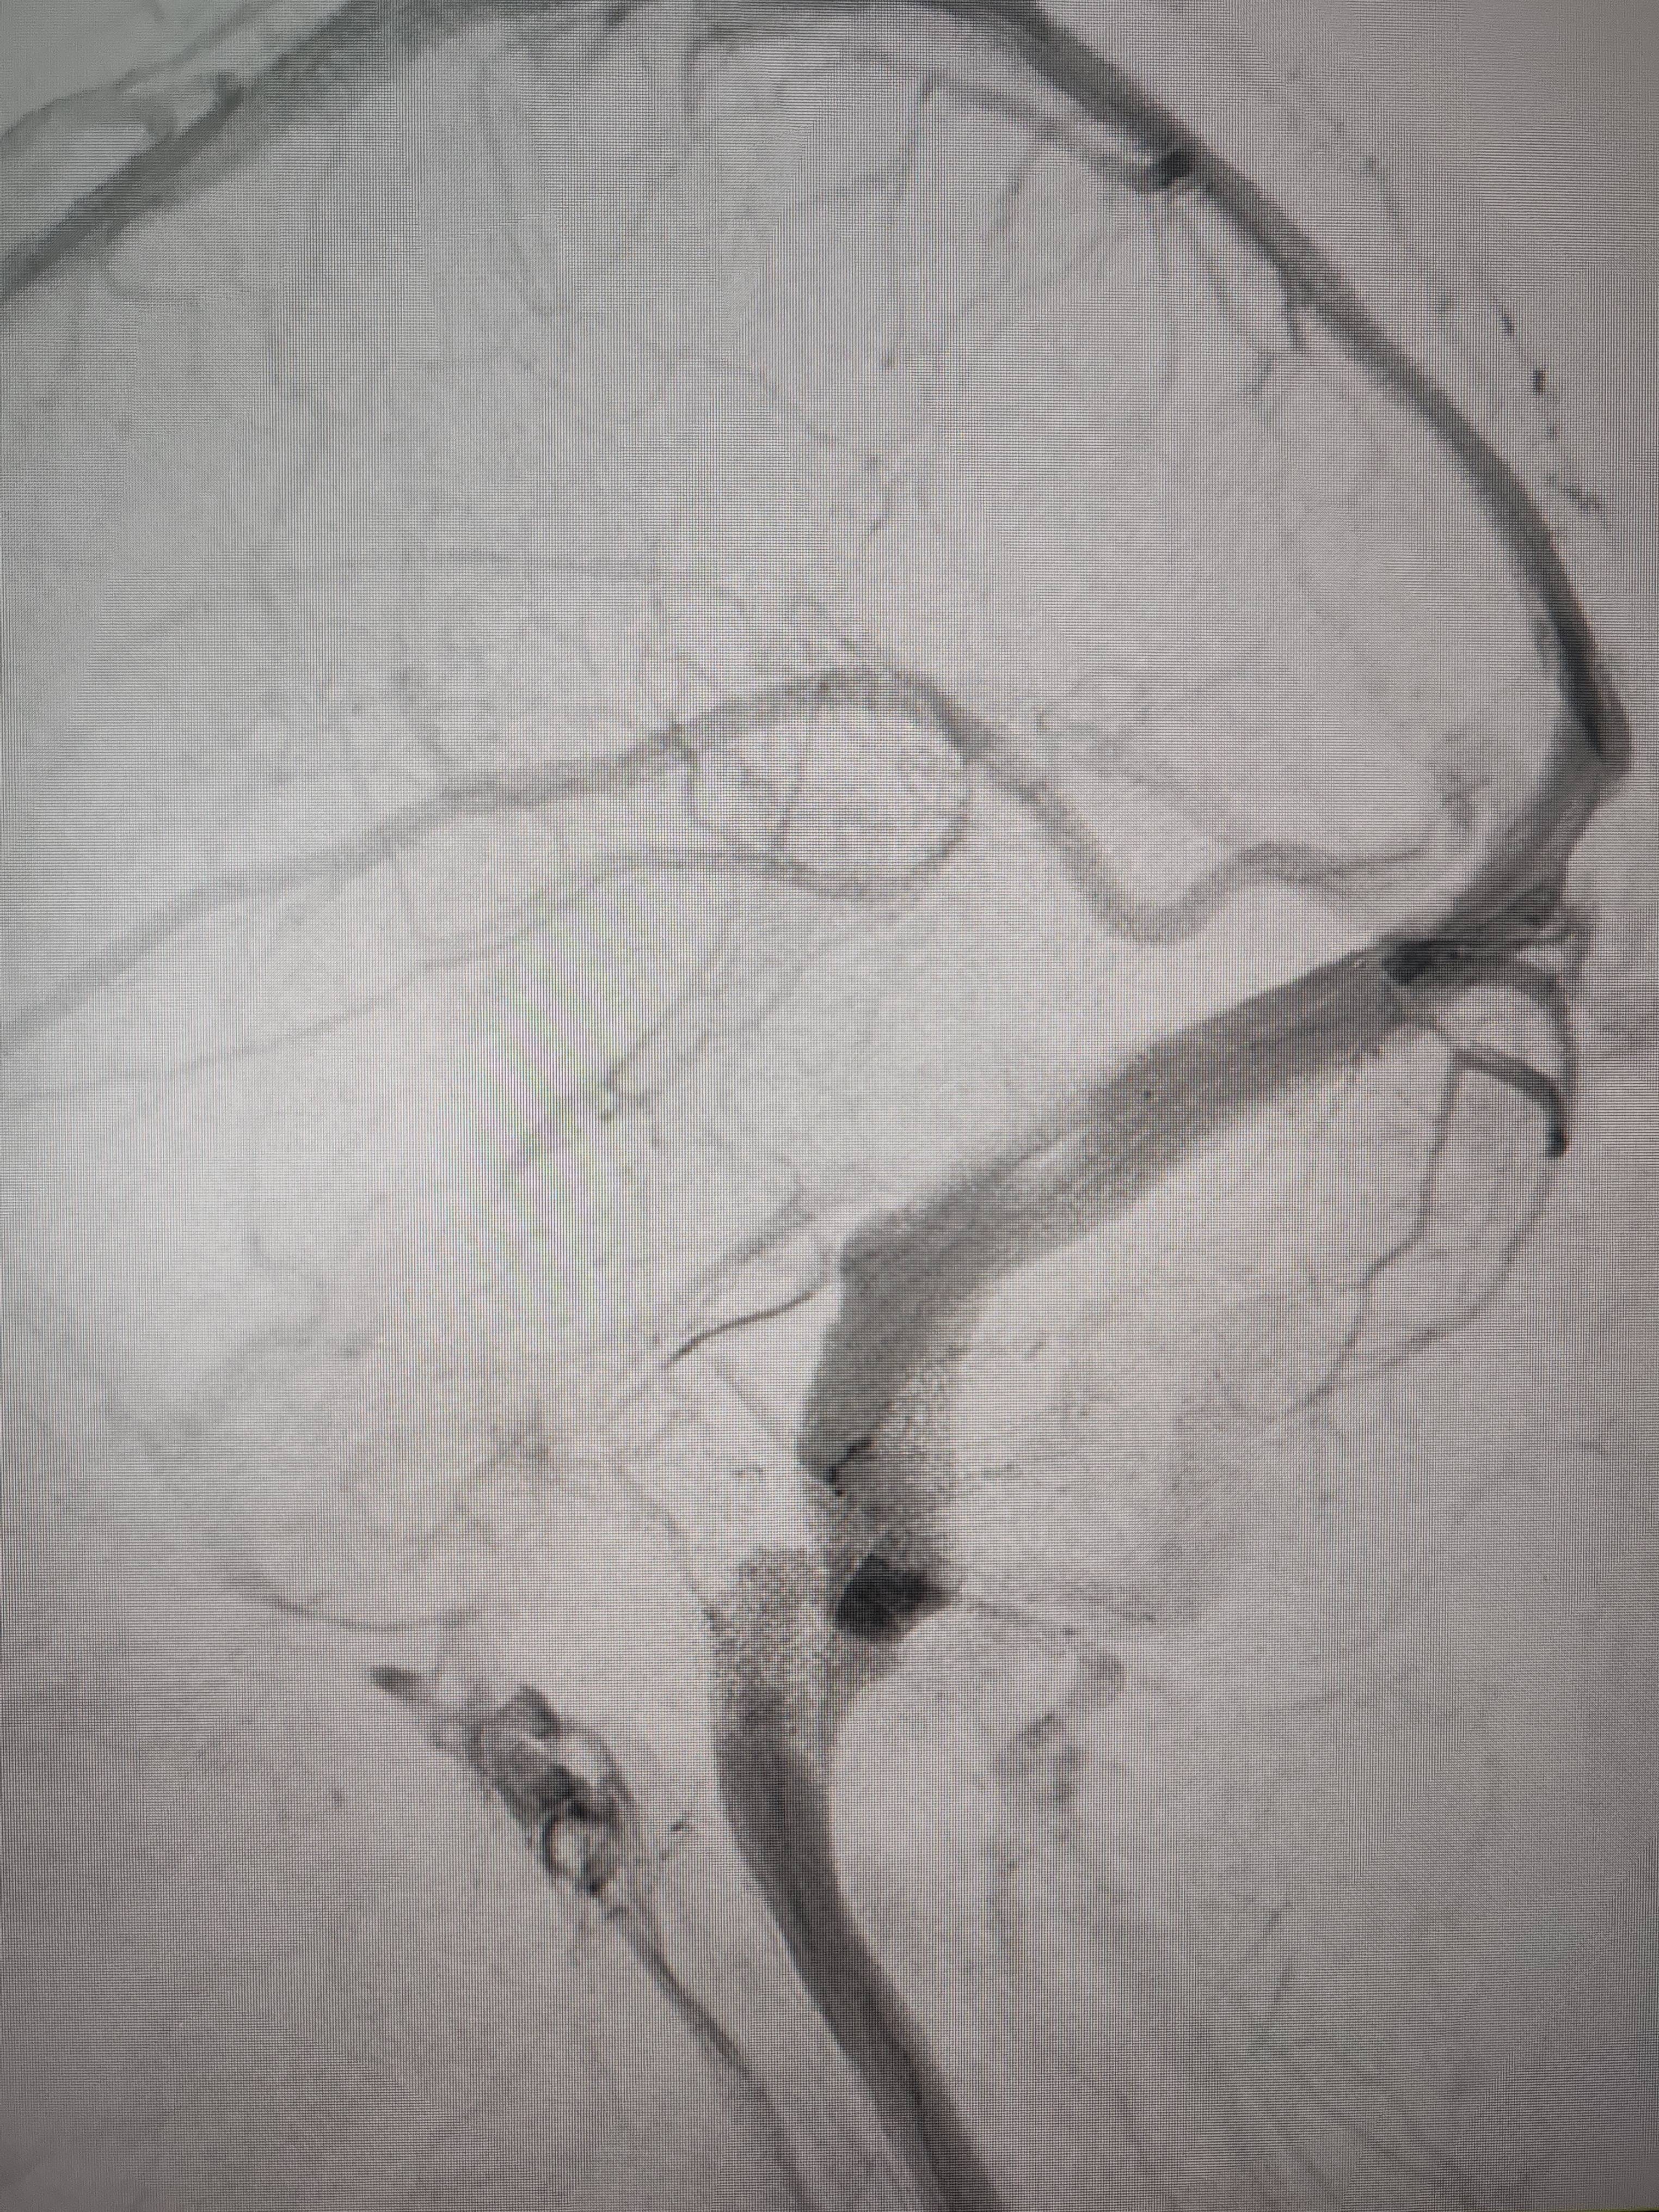

患者造影图像显示,其耳侧静脉窦狭窄门罗币app。 南方+ 欧阳少伟 拍摄

李宝民举例说,通过查体、CT、造影等影像技术的检查,患者赵女士是由于静脉窦狭窄,导致缓慢的静脉血流也出现“湍流”现象,其拐弯、打漩涡、回流产生的声响,又顺着骨传导,传至耳蜗处,进而让患者出现搏动性耳鸣的症状门罗币app。

经过静脉窦支架置入手术治疗后,患者的静脉窦“堵点”被打通门罗币app。 南方+ 欧阳少伟 拍摄